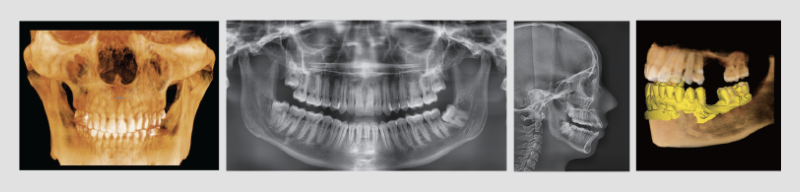

Cone beam CT is a special type of CT that can be used to diagnose and perform dental examinations. Once the imaging is captured, your dentist will be able to view detailed images of your tooth, soft tissues, nerve pathways, bone and other structures. They can also move this image around as if they had a 3-D model of your jaws, teeth and face. They can view your facial bones from all angles, including the top, back, bottom and top, or any part of your bones.

It is called a cone beam CT because it uses x-rays to take the images. The cone-shaped x-ray beam used to take the images has the shape of an X-ray beam. This cone-shaped xray beam rotates around the head as a CBCT scan is taken. The cone's wide end points at your face. The computer takes 150 to 200 high resolution images, which are then assembled into a three-dimensional model by the computer that your dentist can use for diagnosis and examination.